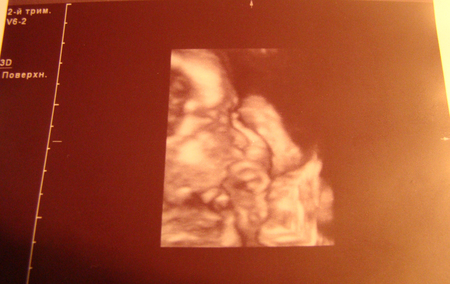

Самочувствие отличное, действительно наслаждаюсь своим состоянием. Правда довольно много набираю веса. Уже 8 кг. ((( Ну и плевать - раз чувствую себя хорошо и не отекаю, значит все нормально. На днях ходили на УЗИ. У наса будет ДОЧКА, маленькая принцесса.... Мы так счастливы.... Теперь уж мой сон про Кузю точно не сбудится ))))

Пока делали УЗИ папа наш наблюдал и расплывался в улыбке, а малышка в это время сосала пальчик. Потом нам все показали в формате 3 D... так было приятно ее увидеть